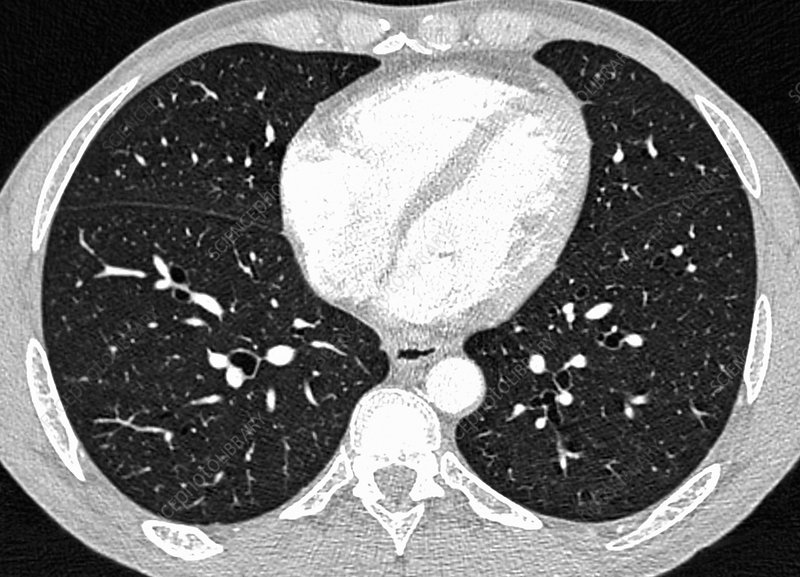

CT Quality Assurance and Protocol Optimization

Comprehensive training on CT quality assurance, dose optimization, and protocol development for medical physicists and technologists.